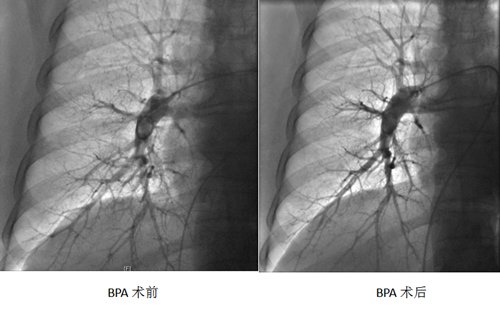

近日,山东大学第二医院心血管内科肺血管团队在主任鹿庆华的带领下,为一位慢性血栓栓塞性肺动脉高压(CTEPH)患者实施了经皮肺动脉球囊扩张成形术(BPA),这是医院首次对CTEPH患者实施此类手术。

手术在局麻下穿刺右股静脉,置入指引导管后,应用不同直径的扩张球囊分次、逐级对肺动脉段水平的病变血管进行扩张。术中患者无明显不适,患者氧饱和度在术中就逐渐上升,肺动脉压力也明显下降。

CTEPH是因肺动脉血栓栓塞导致肺动脉内形成机化血栓、肺动脉狭窄、闭塞、重构等病变,从而影响肺循环灌注。BPA手术通过扩张肺血管低灌注区,重建有效肺血管,改善肺循环,改善通气—灌注匹配,降低肺动脉压力,改善右心功能。BPA手术可在肺动脉高压靶向药物基础上进一步降低肺动脉压力,改善疾病预后。